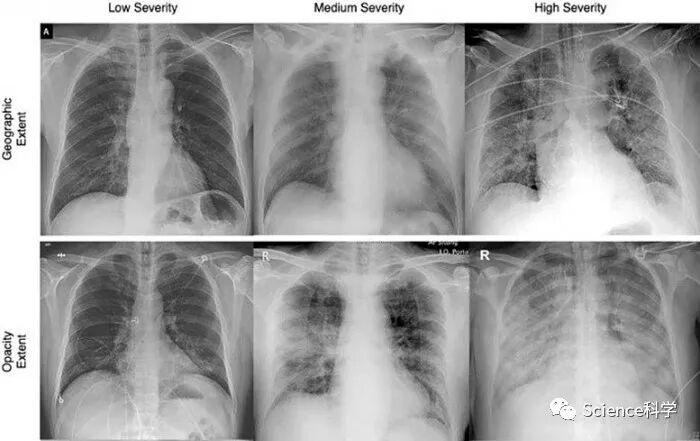

滑铁卢大学研究人员开发的人工智能(AI)技术能准确评估COVID-19病例的严重程度。这项于一年前发起、有滑铁卢大学及其衍生初创公司DarwinAI的研究人员、纽约州立大学石溪分校医学院和蒙特菲奥里医疗中心的放射科医生参与的研究为COVID-Net开源项目的一部分。

研究人员通过对深度学习AI进行训练从而根据胸片分析COVID-19患者肺部感染的程度和不透明度,然后将其得分跟放射科专家对相同X射线的评估进行比较。结果显示,在感染严重程度和不透明度这两个重要指标方面,AI软件做出的预测跟人类专家提供的得分吻合良好。

系统设计工程学教授、DarwinAI联合创始人Alexander Wong表示,这项技术可以为医生提供一个重要的工具以帮助他们管理病例。

他说道:“评估COVID-19患者的严重程度是临床工作流程中确定治疗和护理的最佳行动方案的关键步骤,无论是让患者入住ICU、给患者吸氧治疗还是让患者使用机械呼吸机。这项研究的有前景的结果表明,AI具有强大的潜力来成为支持一线医护人员做出决定和提高临床效率的有效工具,考虑到当前的大流行给全球卫生保健系统带来的巨大压力,这一点尤其重要。”